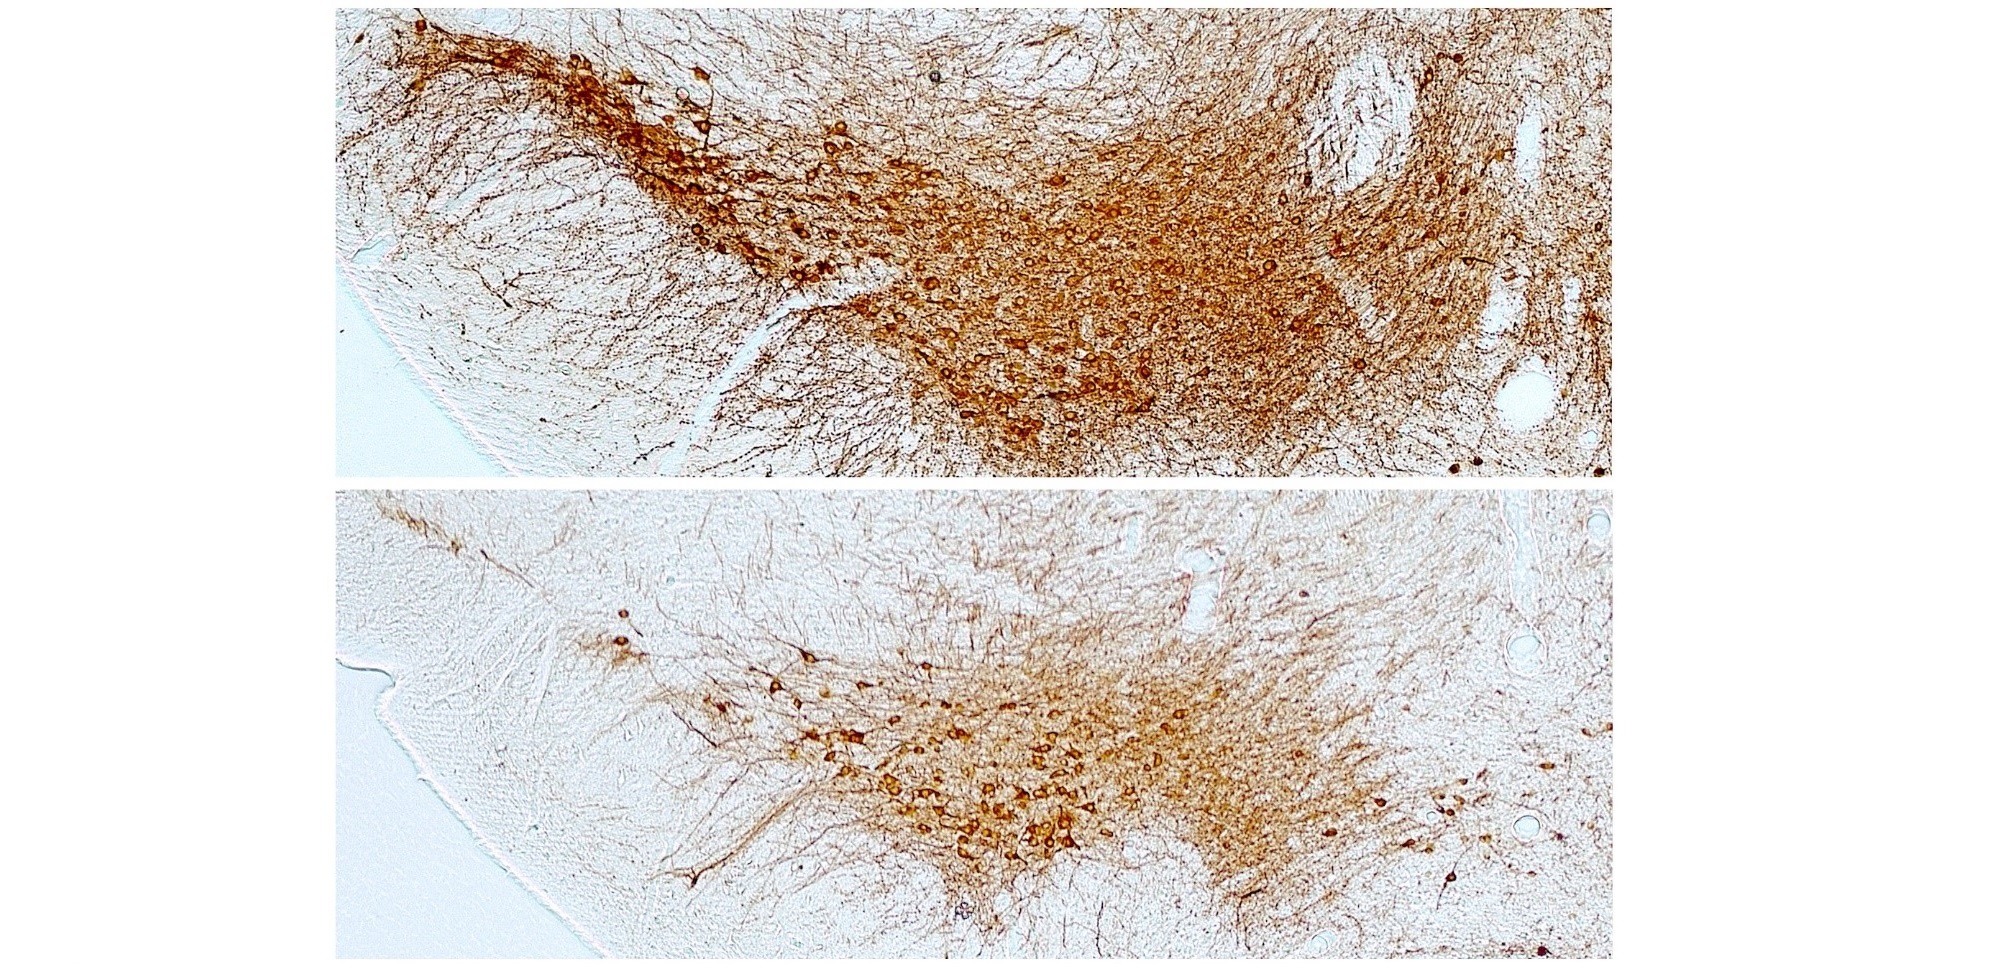

El metabolismo energético cerebral conecta el consumo de cannabis con la insociabilidad

07/08/2020